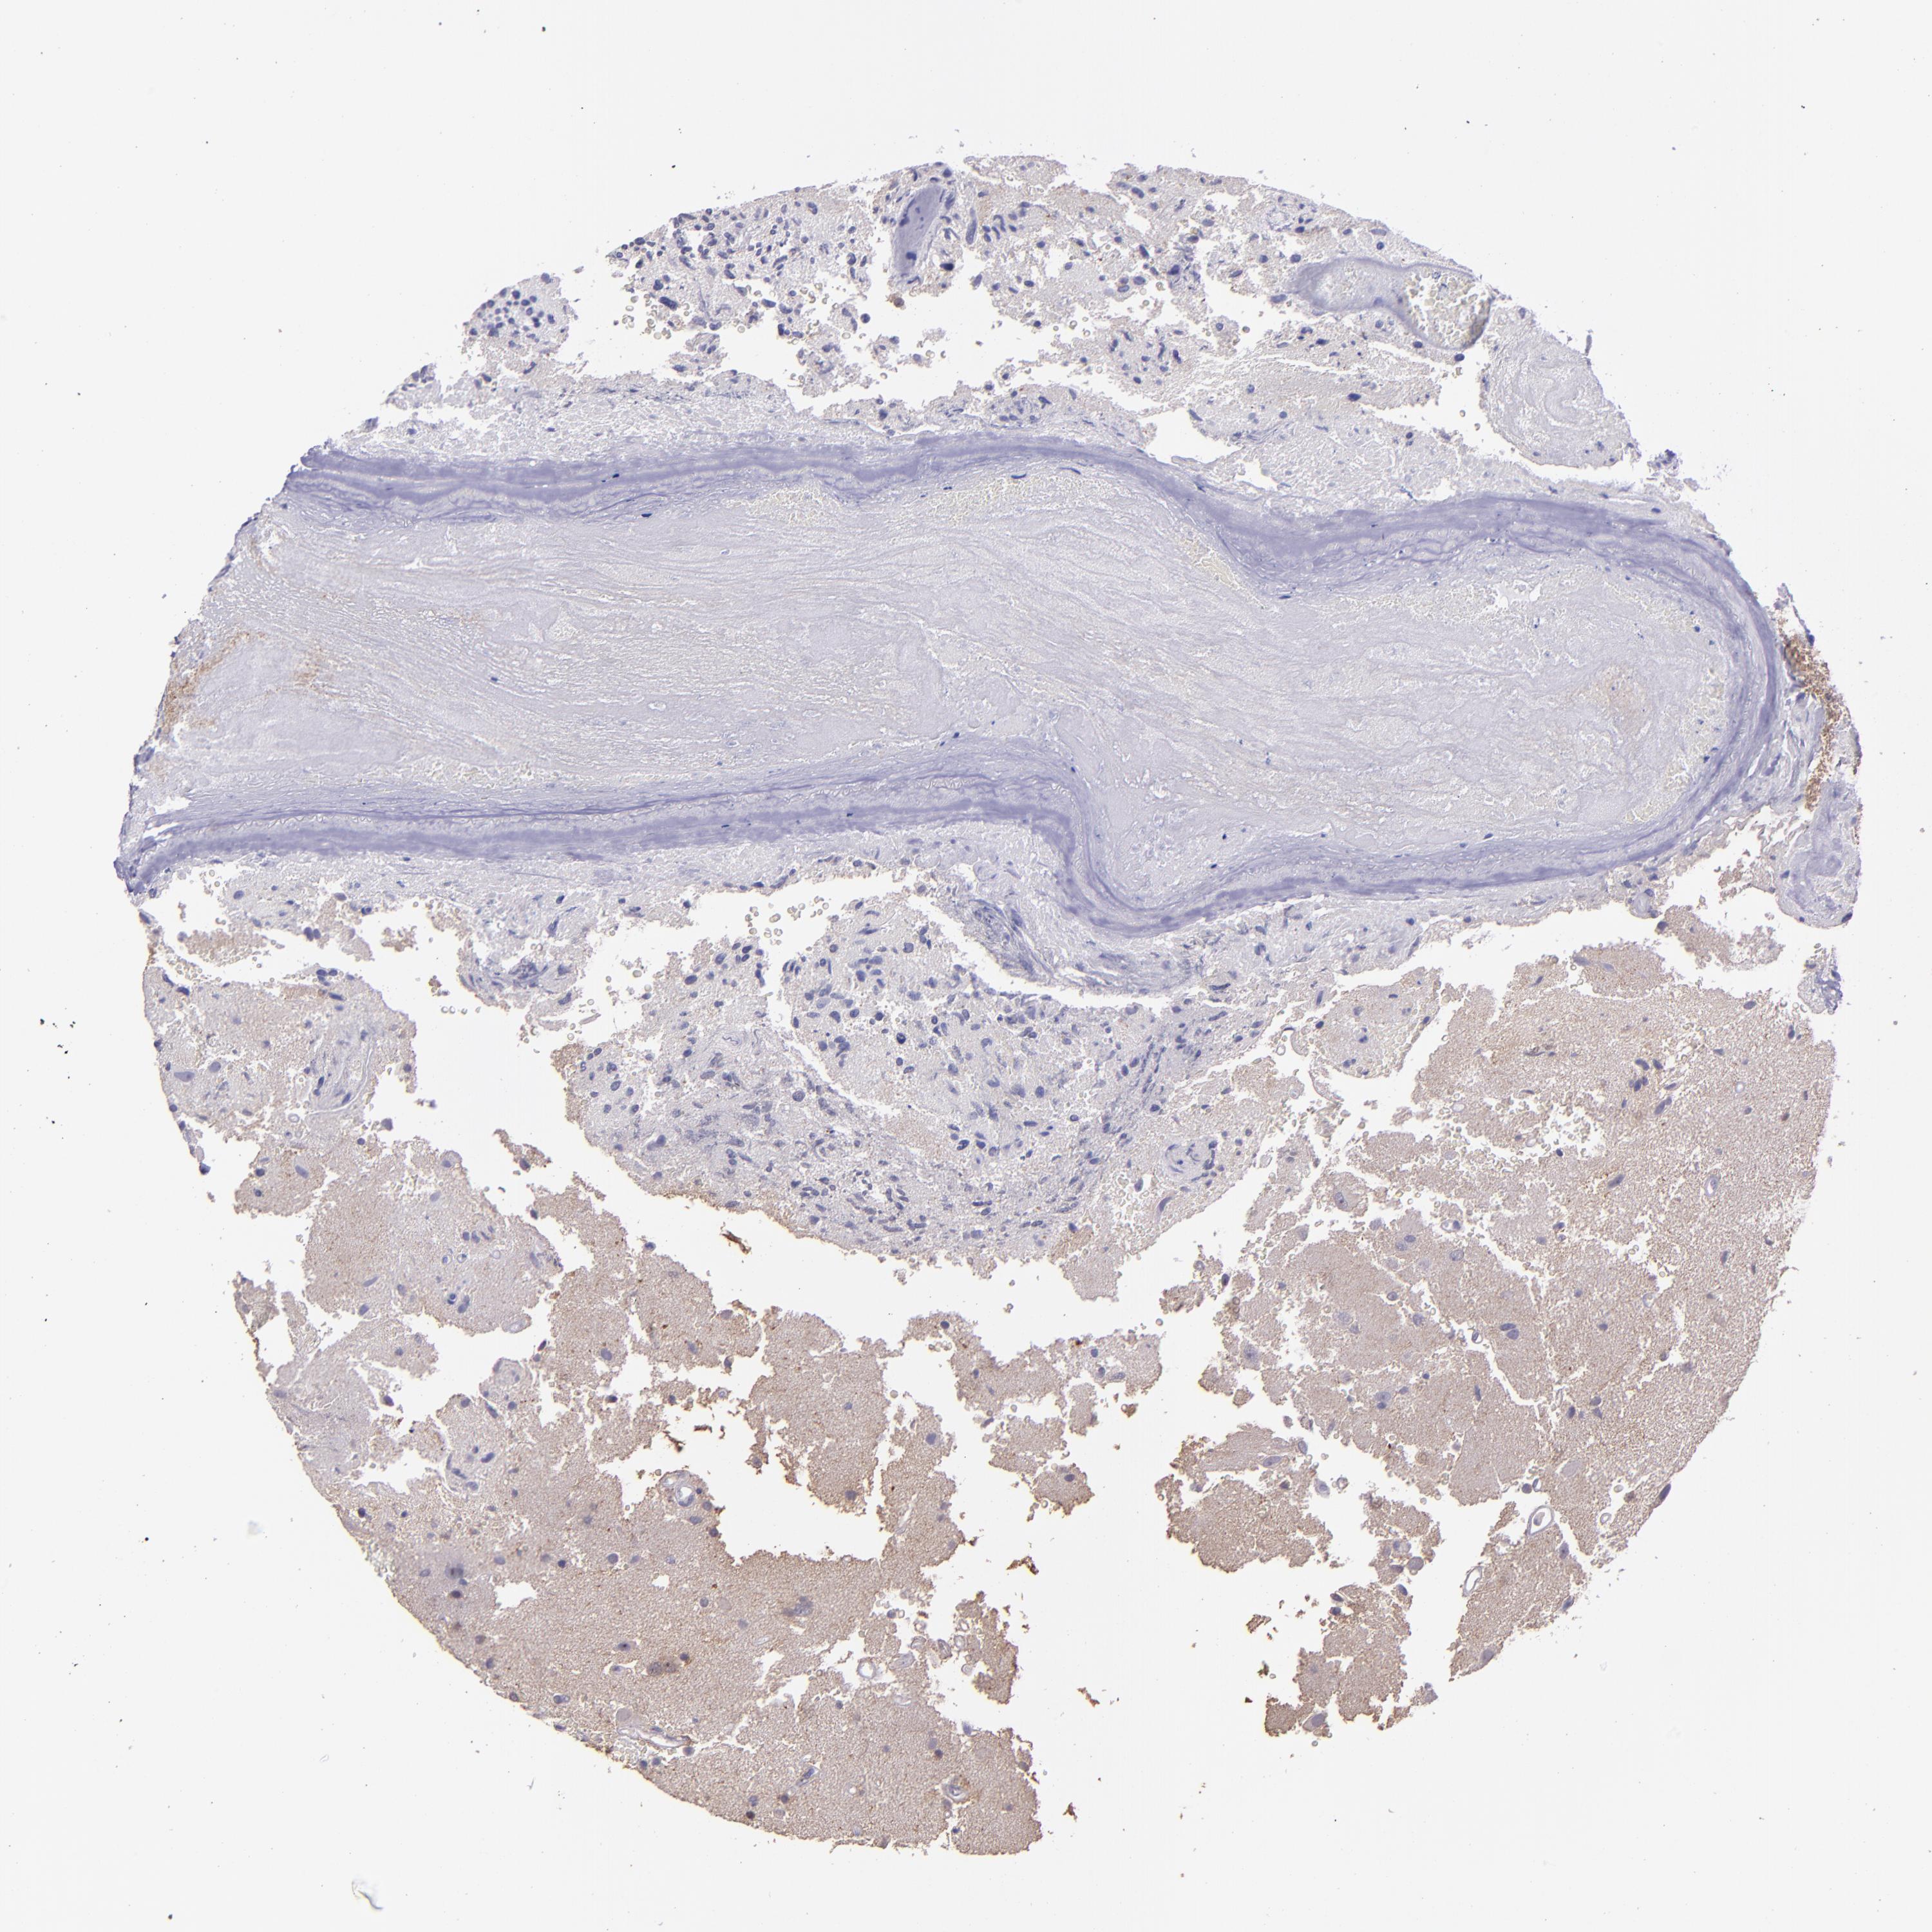

GLIOMA - Protein expressioni

A mouse-over function shows sample information and annotation data. Click on an image to view it in a full screen mode. Samples can be filtered based on level of antibody staining by selecting one or several of the following categories: high, medium, low and not detected. The assay and annotation is described here.

Note that samples used for immunohistochemistry by the Human Protein Atlas do not correspond to samples in the TCGA dataset.

Antibody stainingi

Antibody staining in the annotated cell types in the current human tissue is reported as not detected, low, medium, or high, based on conventional immunohistochemistry profiling in selected tissues. This score is based on the combination of the staining intensity and fraction of stained cells.

Each image is clickable and will lead to virtual microscopy that enables deeper exploration of all samples and also displays staining intensity scores, fraction scores and subcellular localization as well as patient and tissue information for each sample.

Antibody HPA001667

Antibody CAB016724

Staining

High

Medium

Low

Not detected

Intensity

Strong

Moderate

Weak

Negative

Quantity

>75%

75%-25%

<25%

None

Location

Nuclear

Cytoplasmic/membranous

Cytoplasmic/membranous,nuclear

Glioma, malignant, High grade

Glioma, malignant, Low grade

Glioma, malignant, NOS